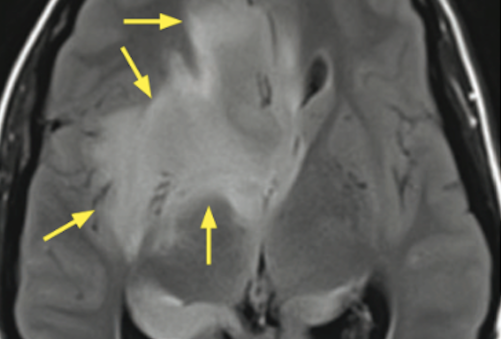

Glioblastome (grade IV)

- Peu de chance de survie (15mois médian)

- Oedème (mélange entre infiltration + oedème vasogénique)

- Meilleur signe pour la récidive = La prise de contraste

- Nécrose centrale

- Hémorragies

Agressive, mal délimitée